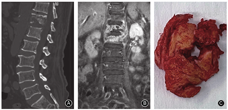

椎间盘被累及是支持化脓性脊柱炎的有力证据[10,11]。我们在手术过程中经常发现化脓性脊柱炎患者的椎间盘往往破坏严重,椎间隙充填着炎性坏死组织(图2A,B);而脊柱结核患者的椎间盘比较完整,可连同软骨终板一起整块切除(图2C,D,图3)。文献报道61%脊柱结核患者椎间盘得到保留,而化脓性感染患者的保留比例仅6%[9]。对椎间盘破坏程度的研究也显示,57.5%的结核患者椎间盘无破坏或仅轻度破坏;而化脓性感染患者中椎间盘完整者仅为3%[9]。对于化脓性脊柱炎破坏关节软骨,细菌释放蛋白水解酶可酶解破坏椎间盘和软骨终板;而结核杆菌由于缺乏蛋白水解酶,因此椎间盘可得到较好地保留[8]。

椎体骨破坏是支持脊柱结核的有力证据[13]。结核患者椎体骨破坏比较严重,椎体内形成明显的死骨,因此外科手术时往往选择椎体次全切除进行清创和重建(图4);而化脓性脊柱炎患者的骨破坏往往局限在终板周围,外科手术时更多选择椎间盘连同软骨终板和周围死骨切除清创后,行椎间隙植骨融合(图5)。有学者分析了33例结核和33例化脓性脊柱炎患者,结果显示54.5%化脓性脊柱炎患者椎体无破坏或轻度破坏(<25%),而结核患者椎体破坏几乎是100%;仅6%化脓性患者椎体破坏>75%,而结核患者比例高达45.4%[9]。所有结核患者均存在椎体骨皮质破坏或丢失,而仅39.3%化脓性脊柱炎存在骨皮质破坏[9,14]。